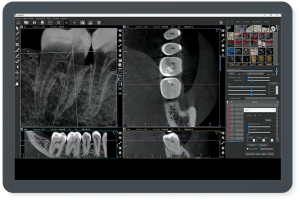

A empresa criou um sistema de radiologia odontológica que proporciona imagens realistas, oferecendo um nível de detalhamento profundo, permitindo a interpretação correta, eficaz e rápida do profissional. “O resultado final é surpreendente. Incrível. Já temos feedbacks extremamente positivos de profissionais renomados em todo mundo”, comenta do criador da empresa, Roney Rocha.

Entre os produtos oferecidos pela CDT Software é o E-VOL DX, reconhecido por pesquisas acadêmicas nacionais e internacionais de odontologia, possibilita imagens mais nítidas e com maior riqueza de detalhes! “O e-Vol DX é um software que supre demanda dos tradicionais aparelhos de radiologia. Compatível com os principais equipamentos do mercado, ele é composto por filtros e ferramentas que transformarão seus laudos”, ressalta.

Além disso, o e-Vol DX está em constante atualização para atender e antecipar-se às demandas dos profissionais da área de radiologia odontológica. Por isso, é um investimento seguro e eficaz e que não estará defasado. Com todos os recursos que garantem obter as melhores imagens de seu tomógrafo, o e-Vol DX possibilita otimizar o tempo de produção com o uso de ferramentas exclusivas.